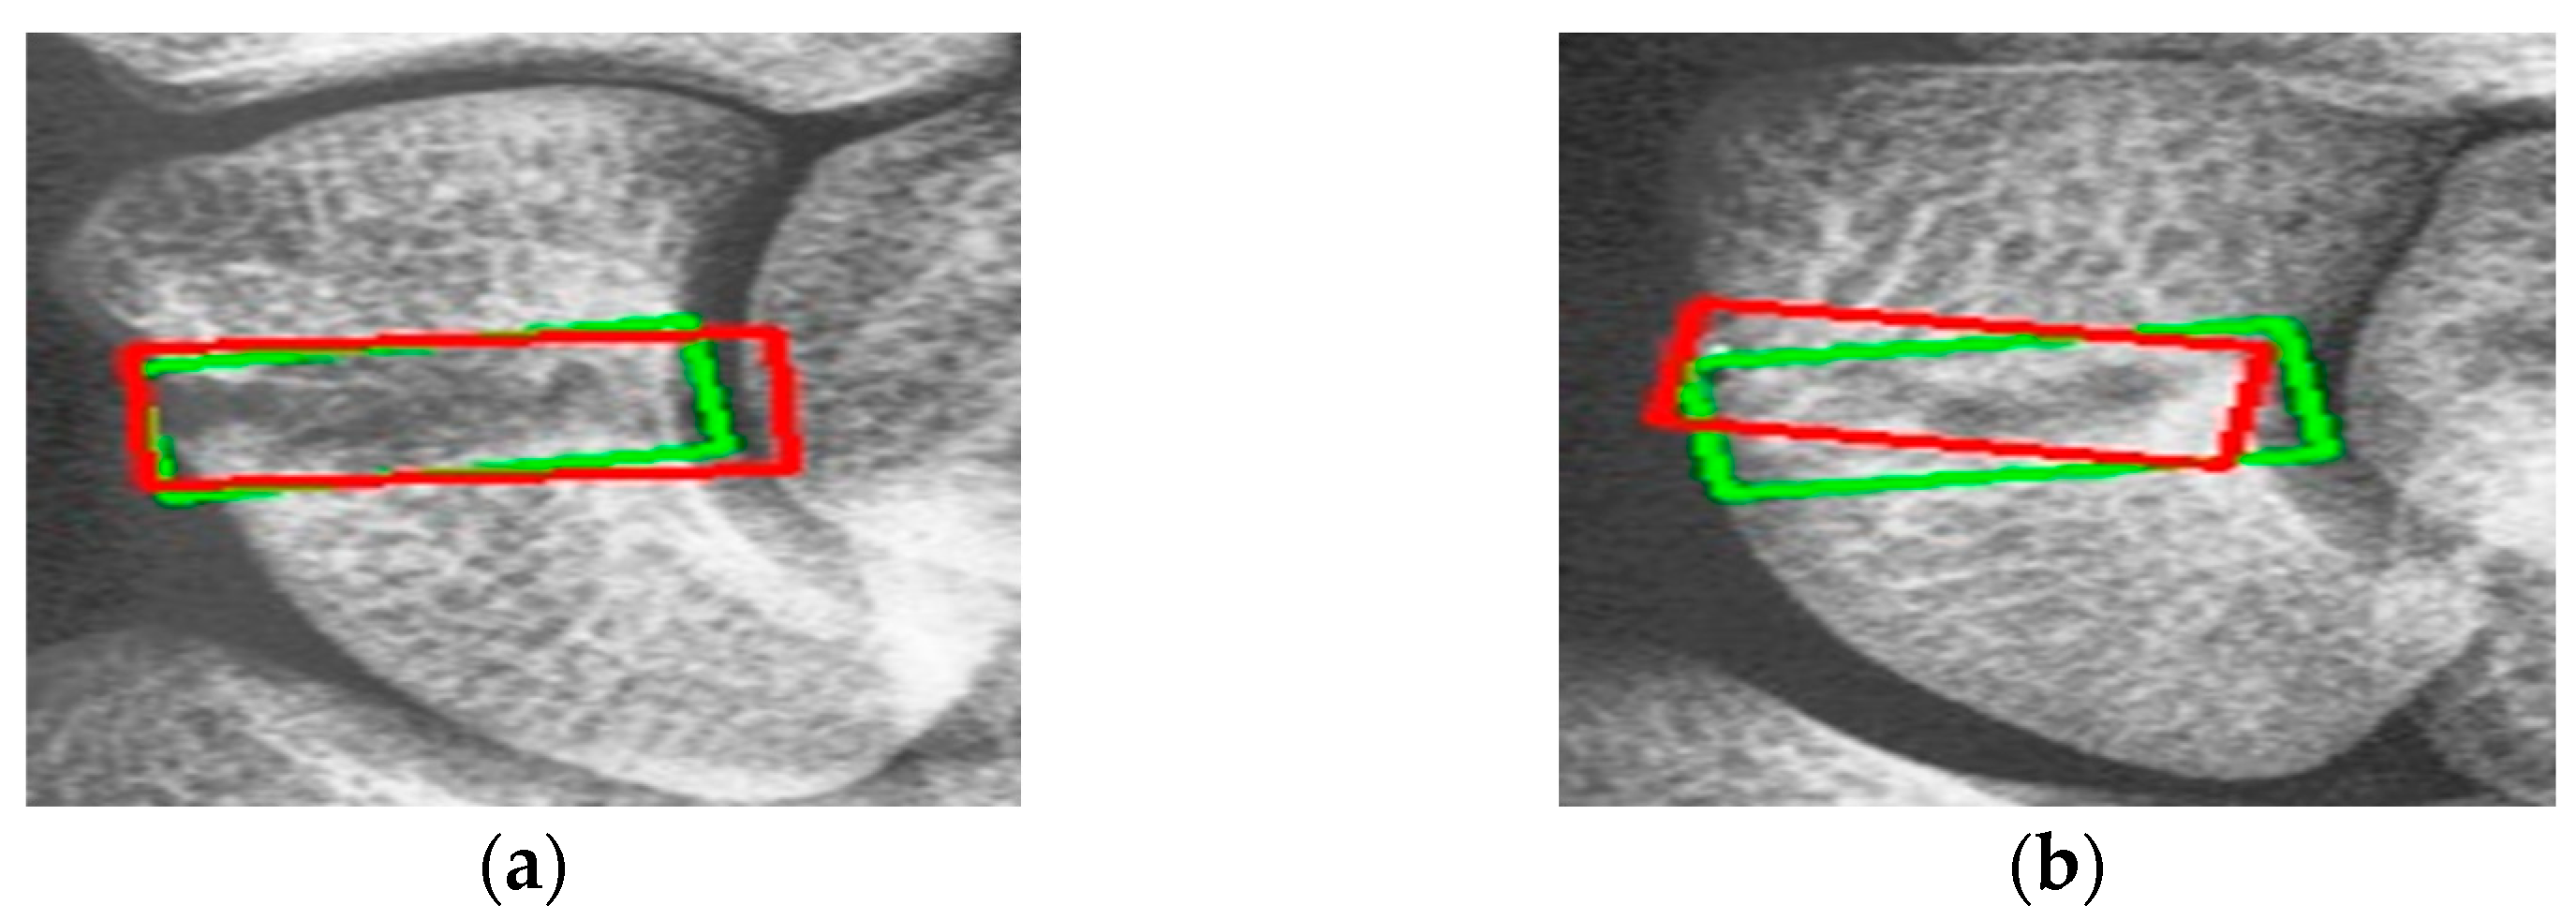

Figure 9 shows the results of scaphoid fracture detection. In the figure, the red area represents the ground-truth box labeled by the doctor, while the green area shows the result predicted by the model. Figure 10 provides an example of a more obvious fracture, whereas Figure 11 illustrates an example of an occult fracture. These examples highlight the challenges in diagnosing scaphoid fractures, as occult fractures are difficult to distinguish by the naked eye. The AP views demonstrate a relatively high IoU, while the LA views also accurately locate the fracture area. This combined approach is effective in drawing the doctor’s attention to the area, enabling quicker identification of the fracture location.

Figure 11. Occult fracture detection visualization. (a,b) Scaphoid bone slices. The red box is the true answer, and the green box is the predicted result.